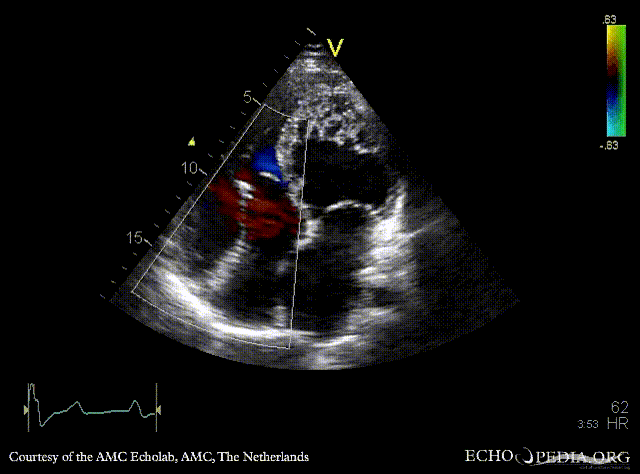

Ebstein anomaly and non-compaction cardiomyopathy

A4CH: high insertion of tricuspid valve, dilated right atrium and right ventricle, non-compaction of left ventricle A4CH with Color Doppler: severe tricuspid regurgitation